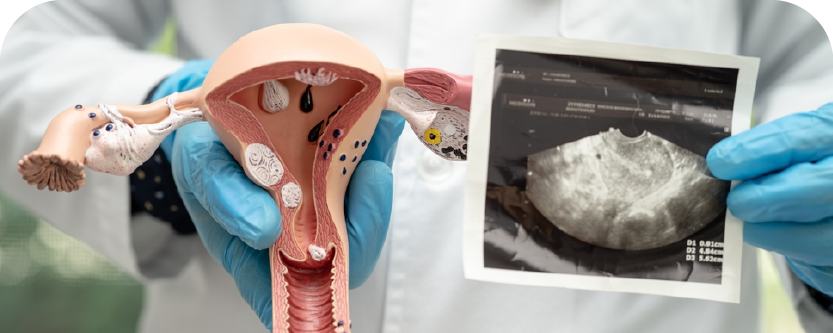

Ketulan Cyst & Fibroid

SEBELUM

SELEPAS